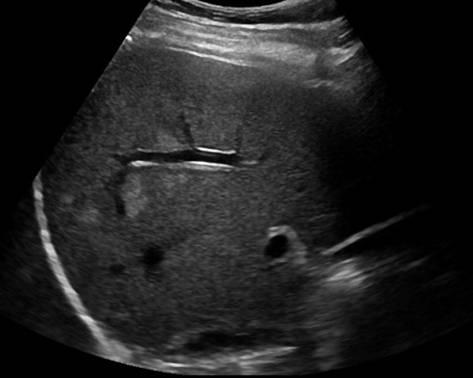

Gan nhiễm mỡ

» Thông tin: Nam giới – 42 tuổi.

» Lâm sàng: Kiểm tra sức khỏe.